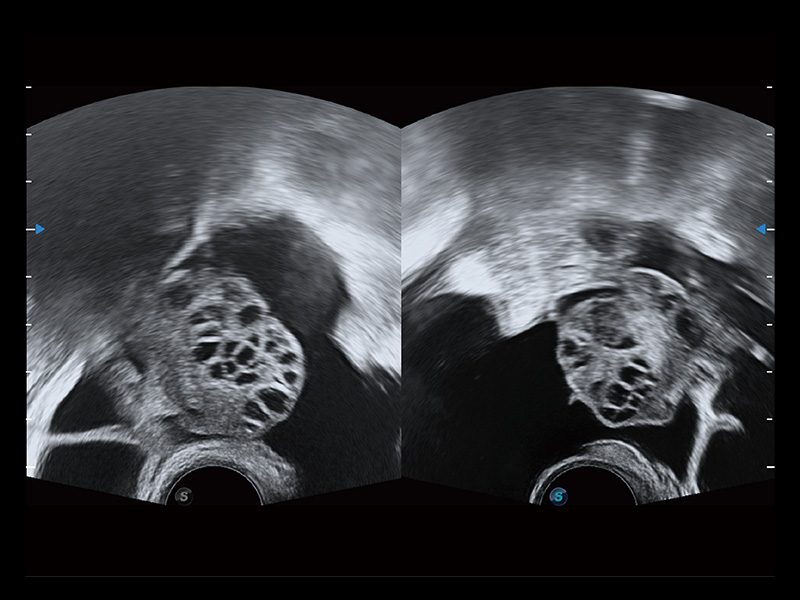

生殖专用腔内探头

曲柄设计方便术者与操作者配合工作。220°大角度扫查配备专用的穿刺架,可清晰显示穿刺针进针过程,保障取卵操作精准与安全。

超声引导下双侧卵巢穿刺取卵

卵巢多囊样改变